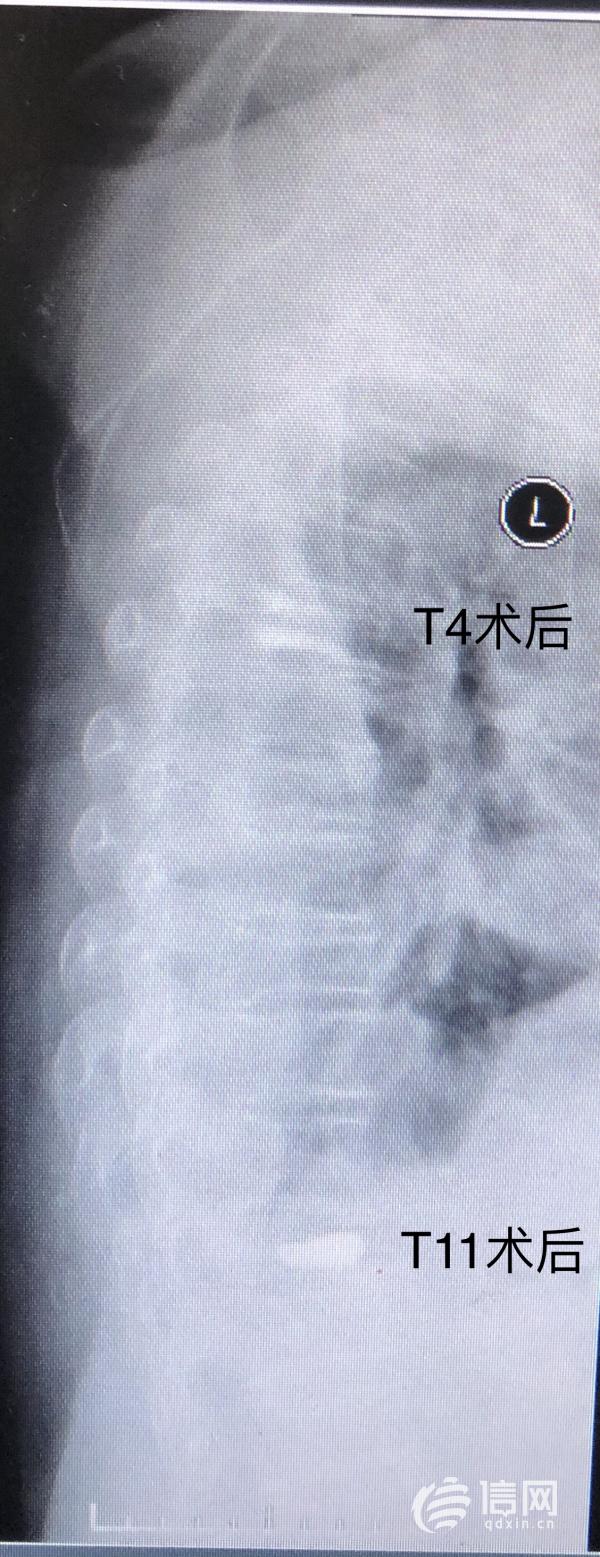

潘雲春副主任醫師建議患者在病情穩定後手術治療,蔡女士及其家人剛開始因高齡老人基礎疾病較多,且聯合損傷存在,老人及家屬對於手術治療比較排斥。潘雲春副主任醫師帶領大家積極討論後決定對蔡女士採用經皮椎骨成形微創手術,儘量減少手術創傷及術後併發症的發生。再次與家人溝通後,得到了家人和蔡女士的理解和支援,局麻下為蔡女士實施了胸4椎體及胸11椎體微創經皮椎骨成形術,手術過程很順利,手術用時60分鐘,基本無出血,刀口3毫米。

當蔡女士被推出手術室的時候,家人高懸著的心也終於放了下來。術後第二天,蔡女士的胸腰背部疼痛明顯緩解,能夠耐受下地行走,飲食及睡眠也因此有了明顯改善,蔡女士也露出了滿意的笑容。

據悉,平度市人民醫院已熟練掌握T5及以下椎體的微創手術(PVP或PKP),潘雲春副主任醫師表示蔡女士的T4椎體壓縮性骨折在術前評估時就面臨著嚴峻的挑戰,對T4椎體在C臂透視下實施微創手術在平度市人民醫院尚屬首例,且T4椎體壓縮骨折合併胸骨體骨折有出現遲發性神經功能障礙的可能,無形中增加了手術的難度,對手術醫師精準的定位,穿刺的力度的大小及角度提出了更高的要求。